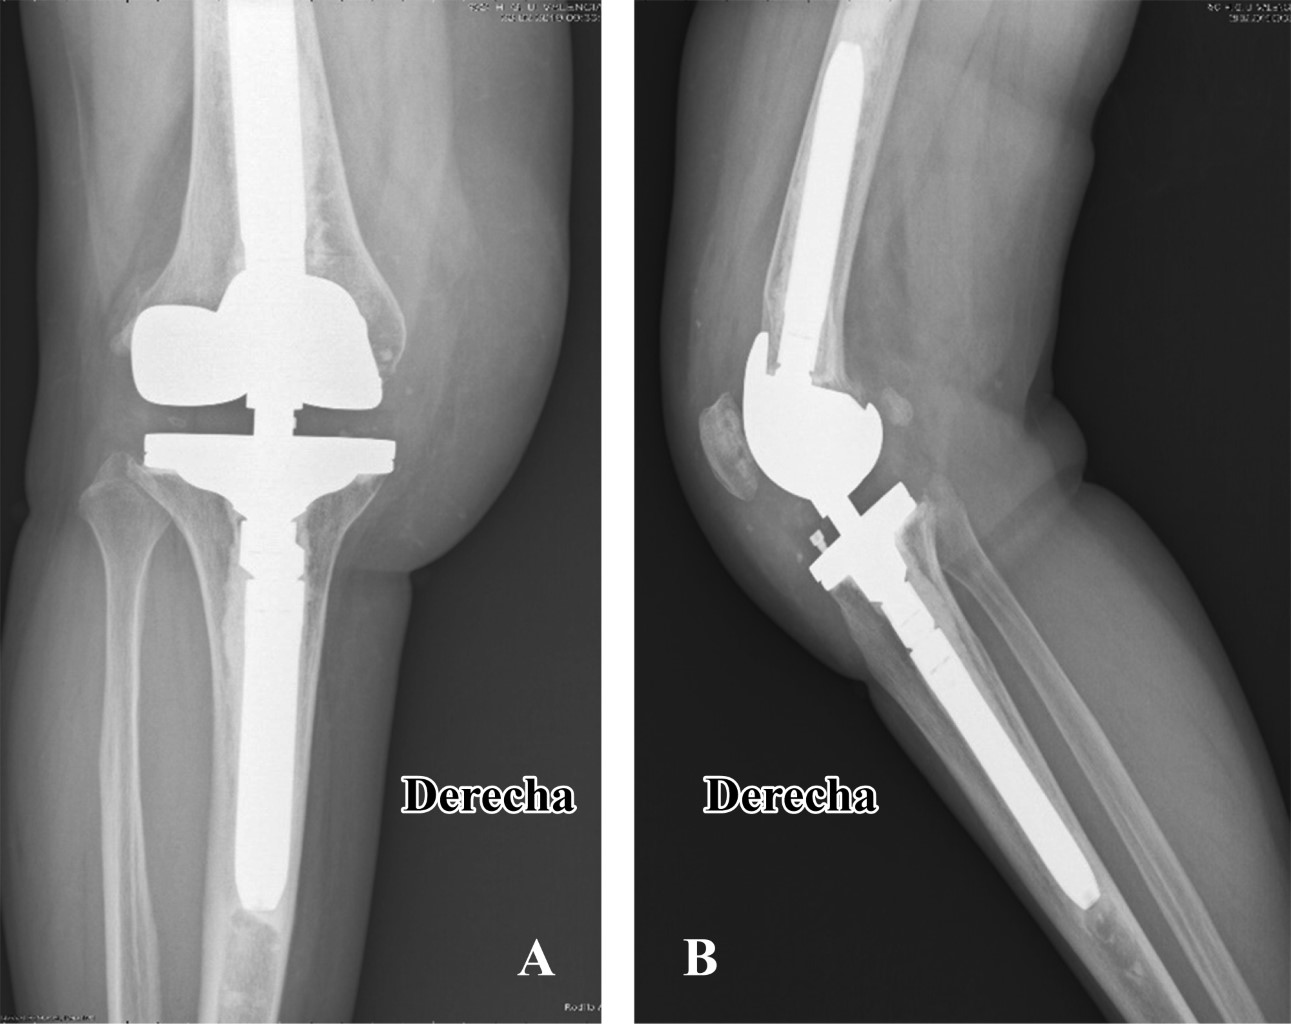

Figure 1